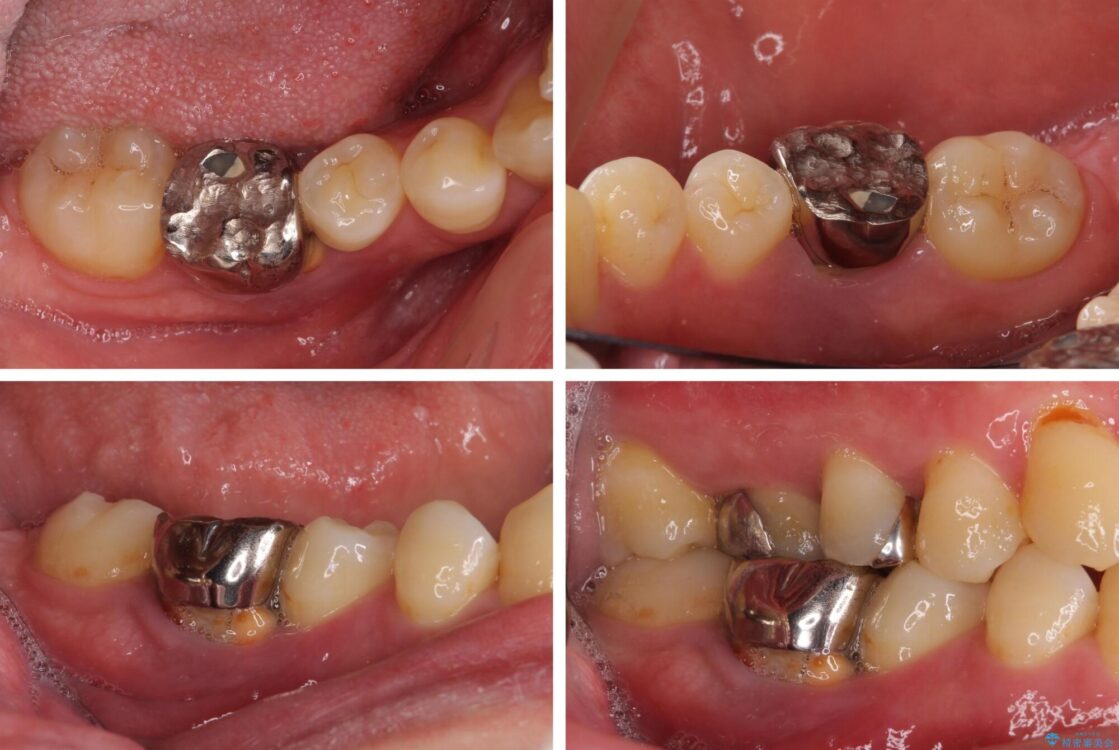

奥歯の痛みと前歯のデコボコを気にして来院された患者様です。

左右下顎の大臼歯は、ともに歯根が破折しており、抜歯が必要な状態でした。

放置したことで炎症による骨吸収が顕著であるため、骨造成を併用してインプラント埋入を行うこととしました。

治療前

• 割れてしまった奥歯とデコボコの前歯 矯正治療とインプラント治療 治療前画像